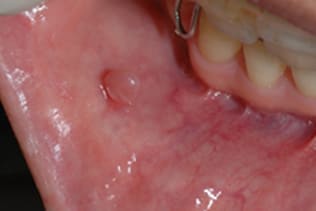

症例1 頬粘膜良性腫瘍(60歳代 女性)

頬粘膜のできものが大きくなり、違和感を認めるようになり気になり来院されました。粘膜組織の突出を認め頬粘膜良性腫瘍と診断して摘出術を施行しました。義歯のワイヤー鈎が刺激になって発生したとも考えます。